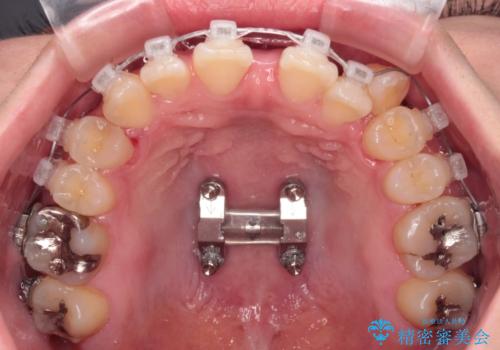

急速拡大装置 狭い上顎骨を拡大してワイヤー装置で八重歯を短期間治療

上顎歯列が狭窄していたため、急速拡大装置により上顎骨を側方に拡大しながら、ワイヤー装置にて矯正治療を行うこととしました。

上顎骨を拡大することで、八重歯やデコボコを歯列に収めることができ、下顎の歯が外に位置していた奥歯の咬み合わせも改善することができました。

スペースも短期間に獲得できるため、1年程度で治療を終えることができました。